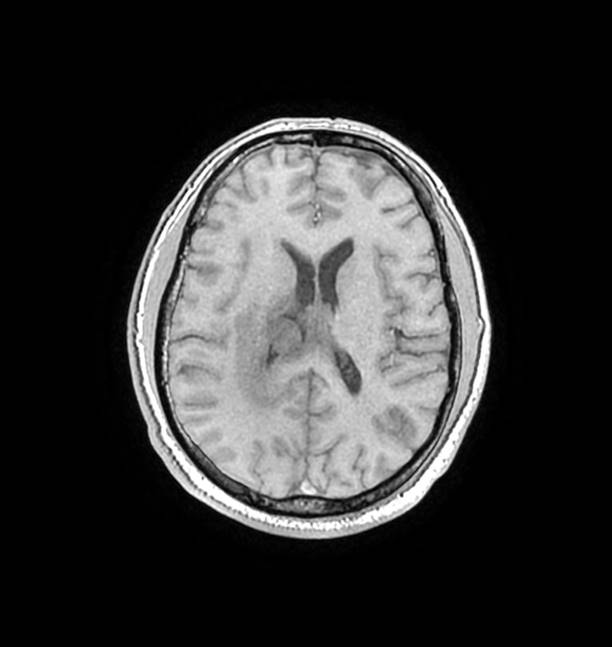

磁共振影像圖

圖1

MR診斷:右側(cè)側(cè)腦室三角區(qū)及側(cè)腦室旁占位,考慮惡性腫瘤可能,間變型腦膜瘤?轉(zhuǎn)移瘤?

MR鑒別診斷

常規(guī)MR檢查是診斷腦膜瘤的有效手段,可以明確腫瘤發(fā)生的部位、形態(tài)和數(shù)目等特征以及病變向鄰近腦實質(zhì)侵犯的程度和范圍,典型腦膜瘤呈等或(和)稍長T1、等或(和)稍長T2信號,??娠@示完整的包膜,增強掃描因腫瘤內(nèi)部新生血管通透性不同呈不同程度強化,由于腫瘤組織的強化程度與腫瘤的惡性程度不完全一致,導致MR常規(guī)檢查在腦膜瘤分級分型方面仍存在一定的困難。擴散加權成像( diffusion weighted imaging,DWI) 及表觀擴散系數(shù)( apparent diffusion coefficient,ADC) 被廣泛用于腦腫瘤的分級、分子分型和腫瘤侵襲性預測,并取得了良好的性能。目前,對于非典型腦膜瘤腦實質(zhì)侵犯的診斷的金標準依賴于組織病理學。